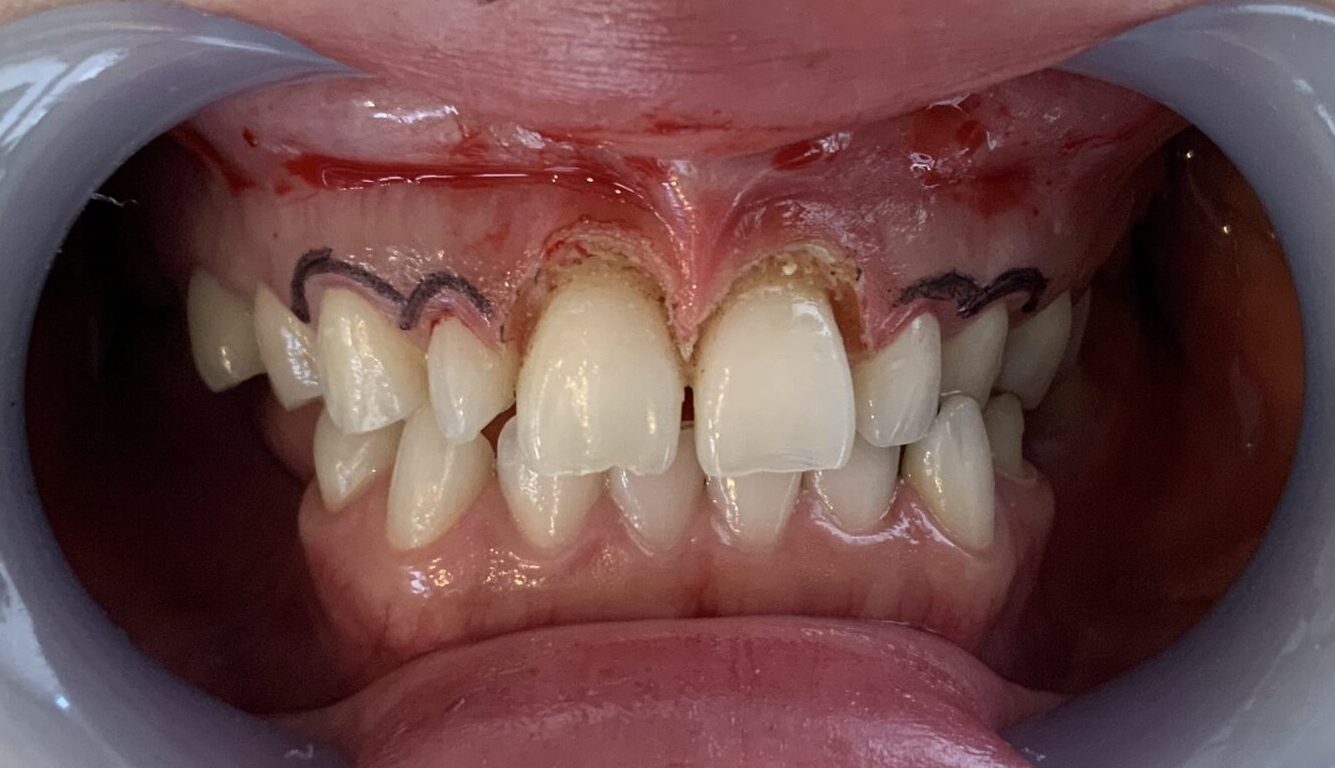

やはり、向かって右側(患者様の左側)の歯は歯槽骨が尖っている部分が認められます。

この部分ですね。

このままの歯槽骨状態では、後戻りをしてしまうので、歯槽骨整形を追加して治療します。(追加費用はありません。)

全ての歯の手術を終えて終了です。

こんなに歯が大きくなり、歯ぐきが小さくなり、ガミースマイルも改善しました。

笑った時に歯ぐきが丸見えの状態は改善されました。